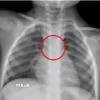

Trước đó, ngày 10/12, bệnh nhi được đưa đến Bệnh viện Sản Nhi tỉnh Phú Thọ trong tình trạng tím tái, quấy khóc, có dấu hiệu khó thở. Qua thăm khám lâm sàng tại Khoa Cấp cứu, các bác sỹ nghi ngờ trẻ bị dị vật đường ăn mắc tại thực quản và khẩn trương chỉ định chụp X-quang.

Kết quả chẩn đoán hình ảnh ghi nhận một dị vật kim loại mắc trong thực quản, nghi là bộ phận chứa pin cúc áo của đồ chơi. Ngay sau đó, các bác sỹ Khoa Chẩn đoán hình ảnh đã tiến hành nội soi cấp cứu để gắp dị vật.

Ca can thiệp được thực hiện nhanh chóng, chính xác. Cụm pin cúc áo còn nằm trong khay kim loại có kích thước khoảng 2cm đã được lấy ra an toàn, không ghi nhận tổn thương thêm trong quá trình nội soi.